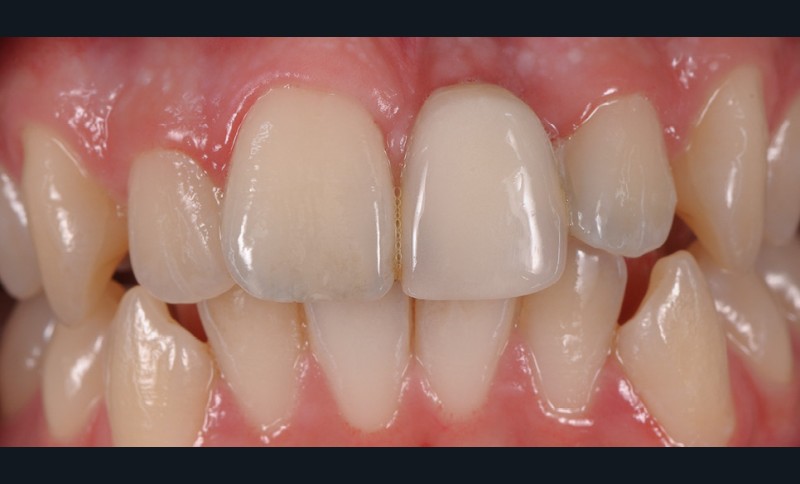

La demande du patient âgé de 20 ans au moment de cette première consultation portait sur la réfection de son bridge collé de type Rochette remplaçant sa 21. Nous avons indiqué dans cette situation clinique la réalisation d’un autre bridge collé, mais de type cantilever en céramique pour tous les avantages qu’ils possèdent.

1/ Qu’anticipez-vous dans le cas de la réfection de ce bridge collé de type Rochette (fig. 1 à 5) ?